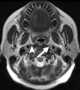

Enlarged lateral retropharyngeal lymph node